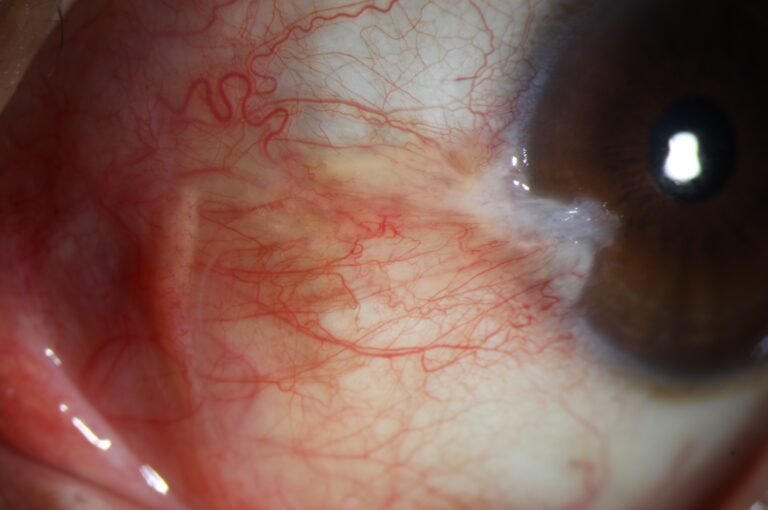

Dry Eye

Full ocular surface analysis

Advanced Dry Eye analysis

Built-in Digital Analysis